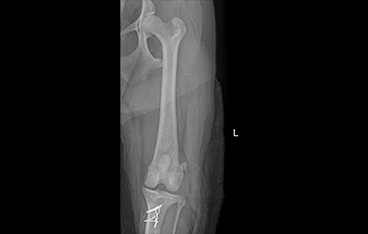

십자인대파열

TPLO, Lateral fabellotibial suture

• TPLO

• TPLO 수술 전

TPLO 수술 후